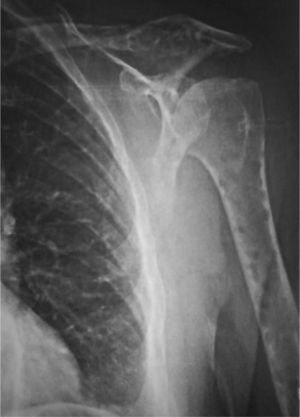

En la radiología simple se evidenciaron lesiones osteolíticas, sin bordes esclerosos de distintos tamaños y sin destrucción cortical en fémures (fig. 1), húmeros (fig. 2), parrilla costal, clavículas y cráneo (fig. 3), sin captación gammagráfica (Tc99) de las mismas.

Ante el diagnóstico diferencial de dichas lesiones (mieloma múltiple, metástasis de carcinoma de mama, pulmón, riñón y tiroides, enfermedad granulomatosa, mastocitosis, enfermedad de Gaucher) se realizó un aspirado de médula ósea que mostró una infiltración por células plasmáticas dismórficas del 23% y permitió confirmar el diagnóstico de MM no secretor (tabla 1).